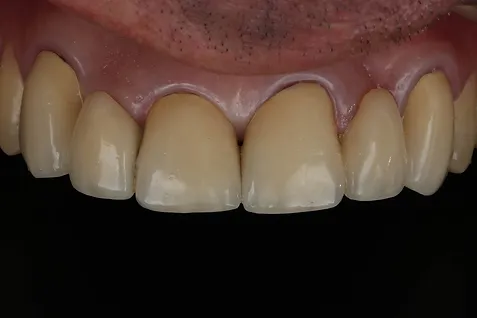

Paciente chegou ao consultório com 2 pontes fixas de 3 elementos cada. O trabalho havia sido feito há aproximadamente 20 anos em metalocerâmica (uma infraestrutura metálica recoberta com cerâmica).

Junto com o paciente optamos pela opção de repetir a ponte. O paciente já estava acostumado ao fato dos dentes serem unidos e era um tratamento mais rápido e com um custo bem menor. Coube a nossa equipe tentar realizar um trabalho que pudesse ficar em boca por mais 20 anos e utilizar o que há de melhor hoje para isso.

Trocamos a liga máetlica convencional por Zirconia para a infraestrutua. Isso vai conferir resistência, melhor propriedade estética e maior biocompatibilidade com os tecidos periodontais.

A peça em metaloceramica na época havia sido cimentada com fosfato de zinco. Hoje tivemos a oportunidade de cimentar com o cimento Multilink da Ivoclar Vivadent, um cimento que possui um primer para Zirconia e consegue aumentar a adesão da peça protética ao dente.